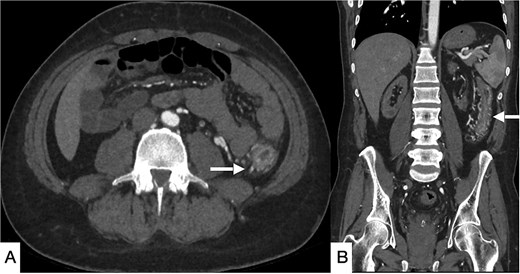

Contrast-enhanced computed tomography (CT) of the abdomen demonstrated long-segment ischemia extending from the transverse to descending colon, characterized by wall thickening, mucosal hypoenhancement, and pericolic fat stranding. A non-occlusive thrombus was noted in the IVC (Fig. 1). Review of prior CT angiography, performed several months earlier for gastrointestinal bleeding, had shown features of colonic angiodysplasia, including mucosal hyperenhancement, early venous filling, and serpiginous submucosal vessels (Fig. 2).

Selected CT angiogram of the abdomen and pelvis in axial (A) and coronal (B) planes showing mild diffuse thickening and mucosal hyper-enhancement of the descending colon, with prominent feeding mesenteric arteries and early draining vein dilation, consistent with angiodysplasia.